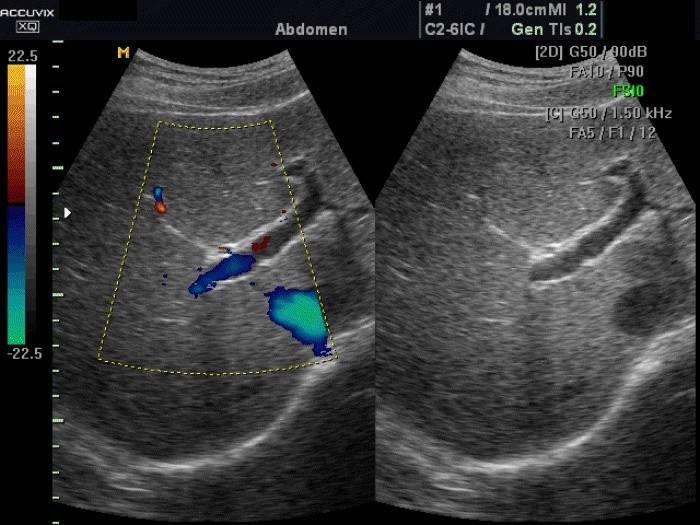

Tento typ diagnózy sa vykonáva na hodnotenie stavu žíl, tepien, ako aj arteriálneho krúžku v oblasti mozgu alebo krku. Ultrazvuková metóda hlavy, krku a krvných ciev je založená na echogenite červených krviniek. Odrazené ultrazvukové vlny sú snímané senzorom. Výsledok sa zobrazí v grafe. Moderné vybavenie umožňuje nielen vidieť stav krvných ciev, ale tiež počuť zvuk prietoku krvi.

Dekódovanie ultrazvukom zahrnuje hodnotenie indikátorov odrážajúcich stav arteriálneho lúmenu, ako aj rýchlosť prietoku krvi. Na detekciu aterosklerotických plakov sa uskutoční vyšetrenie brachycefalických ciev.

V dôsledku ultrazvuku sa diagnostikujú stenóza, kompresia a mŕtvica v cievach hlavy, krku a mozgu. Lekári môžu tiež identifikovať abnormality v obehovom systéme, ktoré vedú k osteochondróze.

Výsledky duplexného vyšetrenia sú nasledujúce:

- hrúbka steny tepny je 0,9 - 1,1 mm;

- svetlosť plavidiel je voľná;

- ak neexistujú vetvy, nedochádza k turbulentnému toku krvi;

- neexistuje patologická sieť žíl alebo tepien;

- vertebrálne tepny sú rovnaké;

- priemer stavcových tepien je viac ako 2 milimetre;

- prietok krvi žilami nie je väčší ako 0,3 m / s;

- žiadne známky stlačenia alebo upchatia.